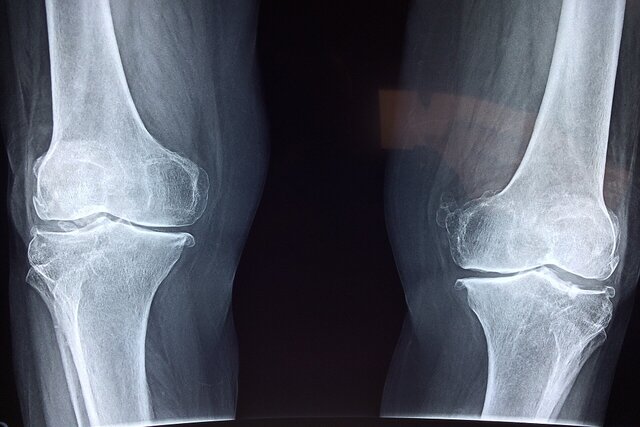

آذربانی در خصوص روش‌های تشخیص بیماری توضیح داد: تشخیص پوکی استخوان با انجام سنجش تراکم استخوان (BMD) یا دگزا (DEXA) انجام می‌شود. این تست ساده و بدون درد، میزان تراکم مواد معدنی در استخوان را می‌سنجد و با کمترین میزان اشعه انجام می‌شود. حتی در زنان باردار نیز در شرایط خاص قابل انجام است. همه‌ خانم‌های بالای ۶۵ سال و آقایان بالای ۷۰ سال باید بدون هیچ پیش‌شرطی این تست را انجام دهند.